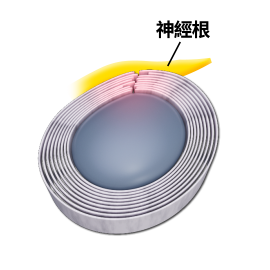

「頸源性疾病」便是指疾病是與頸部問題最為相關。頸是連接頭部與軀幹的橋樑,它包含脊椎、血管 和神經組織(Fig.1),對活動和生存至關重要,任何傷害這條橋樑或這條橋樑出現病患,對維持人體健康或身體機能有關鍵影響。

頸椎結構圖:

(1)上頸椎神經受壓:

因為頸椎分為上頸椎和下頸椎,頸椎C3節為分介線,C3以上椎節為上頸椎節,C3以下椎節為下頸椎節。凡是上頸椎神經受壓,例如:椎間盤突出、椎孔狹窄、椎體移位或下陷,都會有機會導致前額痛、後枕痛、眼窩痛、上頸椎痛。